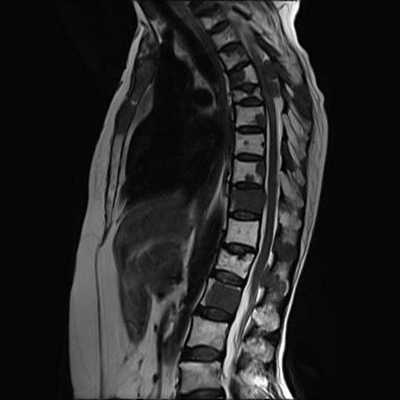

Шейный отдел позвоночника отличается от других большой физиологической подвижностью и минимальной осевой нагрузкой. Ширина позвоночного канала в шейном отделе также существенно меньше чем в нижележащих. В то же время, в шейном отделе рано проявляется спондилез - комплекс дегенеративных изменений в виде обызвествления связок, краевого остеофитоза, артроза дугоотростчатых суставов и унко-вертебральных сочленений. Грыжи дисков в шейном отделе редко бывают большие и медиальные. Хотя при таких грыжах может быть смещение и даже сдавление спинного мозга, они долго протекают бессимптомно. Большинство грыж парамедиальные, которые сопровождаются остеофитами, формируя “твердые” грыжи. При МРТ шейного отдела позвоночника видно, что они часто двухсторонние, сдавливают передний корешок, вызывая типичную корешковую боль вдоль руки. Особенно коварны боковые (фораминальные) грыжи, так как они не всегда отчетливо видны при МРТ шейного отдела позвоночника. Особенно надо отметить, что в шейном отделе позвоночника слабо развита эпидуральная жировая клетчатка, что усложняет визуализацию грыж в аксиальной плоскости на Т2-взвешенных МРТ. Градиентные аксиальные МРТ шейного отдела позвоночника лучше показывают корешок и его сдавление. Сдавление корешка на поперечных МРТ шейного отдела видно как его смещение, отек, стирание четкости границ и, иногда, расширение эпидуральной вены. Спондилез и грыжи дисков приводят к стенозу (сужению) позвоночного канала, нарушения кровообращения по эпидуральным венам и артериям спинного мозга, вызывая его локальный отек и изменения по типу миеломаляции. При МРТ позвоночника в таких случаях виден светлый участок на Т2-взвешенных МРТ. Состояние может быть обратимым, если вовремя оперирована грыжа или проведена сосудистая терапия. Тогда на МРТ нейного отдела позвоночника в сагиттальной плоскости высокий сигнал на Т2-взвешенных МРТ изображениях уменьшается или совсем исчезает. При МРТ в СПб этому симптому мы придаем особое значение, так как он связан с миелопатическим синдромом и говорит о необходимости неотложных лечебных мероприятий.

МРТ шейного отдела позвоночника. Сагиттальная Т2-взвешенная МРТ. Стеноз и миеломаляция.